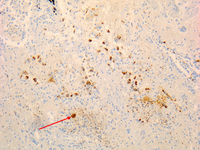

Osteíte por Coxiella burnetii: imuno-histoquímica: a coloração marrom identifica bactérias em monócitos/macrófagos.

Hubert Lepidi, Institut Hospitalo-Universitaire Méditerranée Infection